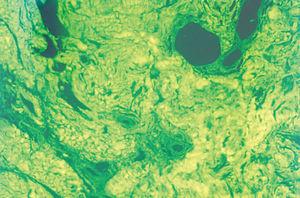

El hemograma, la velocidad de sedimentación globular (VSG), proteína C reactiva (PCR), coagulación, complemento, serología de virus de la hepatitis B y C (VHB y VHC), vitamina B12, ácido fólico, hormonas tiroideas, biomarcadores tumorales, inmunoglobulinas y orina (sedimento e inmunoelectroforesis) no mostraron alteraciones significativas. Las proteínas totales estaban aumentadas: 8,8 g/dl (VN: 6,6-8-3). El estudio electroforético de las proteínas evidenció un aumento de la gammaglobulina: 31,6 % (VN: 12-19 %). No obstante, los estudios de paraproteinemia, tanto en suero como en orina, fueron negativos. El factor reumatoide estaba elevado a 414 U/ml (0-20), y el estudio de autoinmunidad mostró ANA a títulos de 1/640, con patrón granular, anti-SSA/Ro superior a 100 U/ml (VN: 0-25), anti-SSB/La de 99,63 U/ml (VN: 0-25), con el resto de autoanticuerpos dentro de los límites de la normalidad. El estudio histopatológico de la lesión puso de manifiesto una acumulación de material eosinófilo, amorfo y acelular, en los dos tercios superiores de la dermis. Este material se encontraba también depositado en la dermis más profunda a nivel perivascular y perianexial, en donde también existía un discreto infiltrado de células plasmáticas (fig. 2). Las tinciones con rojo Congo y tioflavina fueron positivas (fig. 3), pero el material no se teñía con la proteína A del amiloide. Sin embargo, las tinciones con antisueros de cadenas ligeras κ y λ fueron positivas, demostrando la existencia de células plasmáticas policlonales.

Fig. 3.--Con el microscopio de fluorescencia se aprecia el depósito de sustancia amiloide. (Tinción de tioflavina, x 40.)